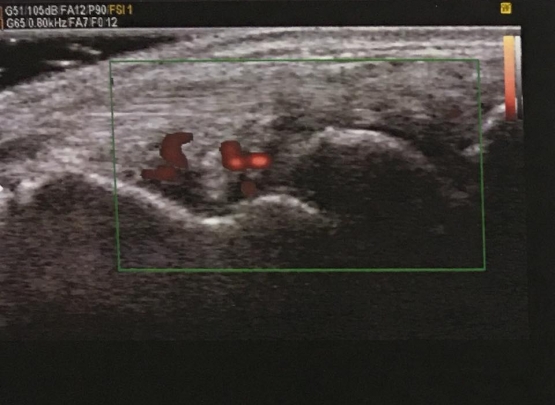

• A presença de inflamação articular mais leve pode passar despercebida ao exame de palpação da articulação. A realização de Ultrassom Doppler por profissional com treinamento específico pode detectar doença ainda ativa (imagem do texto). Isso demandará ajuste do tratamento.